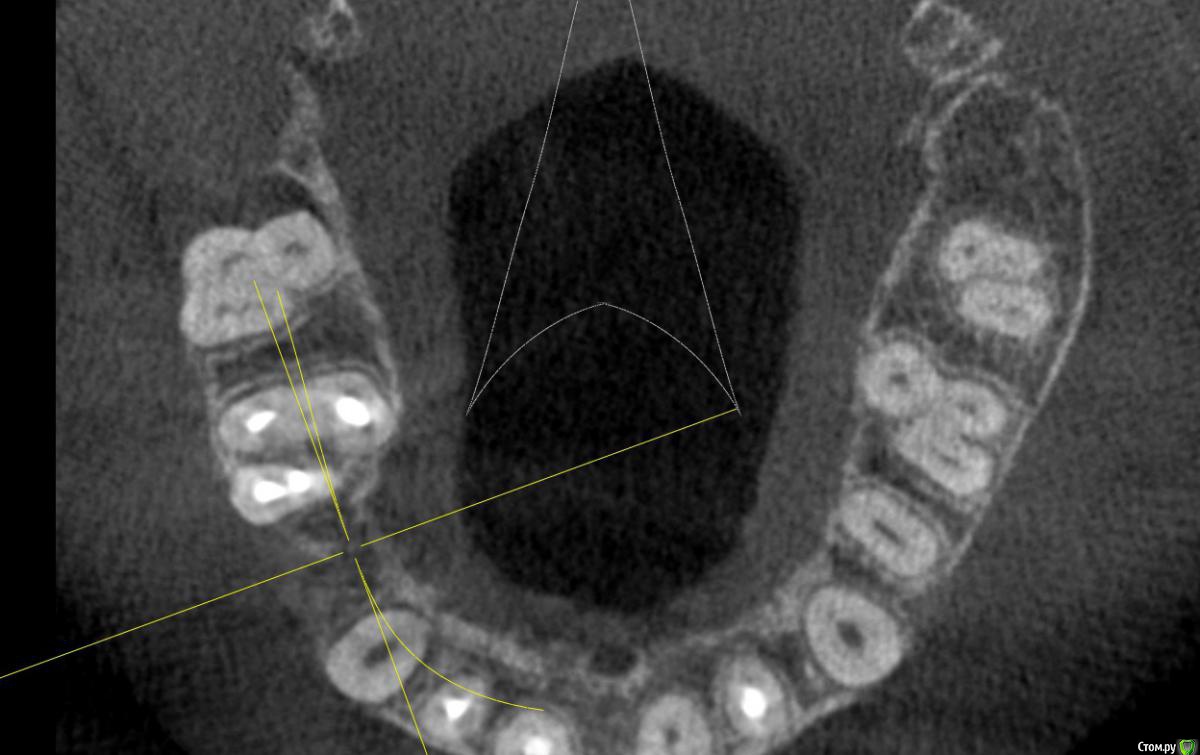

Al..ks Опубликовано 18 апреля, 2019 Поделиться Опубликовано 18 апреля, 2019 Добрый день. Планируется имплантация(15 или 14. брекеты ношу, поэтому не знаю какой будет)+аугментация (в области кармана 17 и при имплантации в случае недостатка кости)+пластика десны+установка формирователя. Все за раз.На выбор dentium, Astra, Nobel, Straumann. Подходят любые и выбор за мной(я склоняюсь к Астре). Правильный выбор? . Плюс ко всему по КТ там отсутствует кортикальный слой( по словам врача) я так понял с наружней стороны, поможет ли аугментация?И поможет ли она с карманом 17? И так как двигали зубы в области корня 11 появилась пустота (толи уже было)в середине лечения и на данный момент Надо ли делать резекцию корня - или канал перелечивать (там ставили СВШ перед брекетами) перед протезирование? Ссылка на комментарий

suballex Опубликовано 19 апреля, 2019 Поделиться Опубликовано 19 апреля, 2019 Добрый день. Планируется имплантация(15 или 14. брекеты ношу, поэтому не знаю какой будет)+аугментация (в области кармана 17 и при имплантации в случае недостатка кости)+пластика десны+установка формирователя. Все за раз.На выбор dentium, Astra, Nobel, Straumann. Подходят любые и выбор за мной(я склоняюсь к Астре). Правильный выбор?Правильный Плюс ко всему по КТ там отсутствует кортикальный слой( по словам врача) я так понял с наружней стороны, поможет ли аугментация?И поможет ли она с карманом 17?Аугментация с карманом не поможет. В остальном - да И так как двигали зубы в области корня 11 появилась пустота (толи уже было)в середине леченияи на данный момент Надо ли делать резекцию корня - или канал перелечивать (там ставили СВШ перед брекетами) перед протезирование?Нужно сравнить КТ начала лечения и последнее. Рентгенологически, канал 11 пролечен хорошо. Возможно, это остаточные явления. Ссылка на комментарий